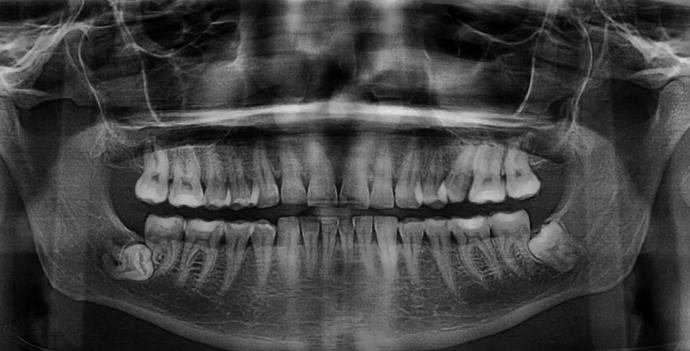

what is the diagnosis?

regional odontodysplasia